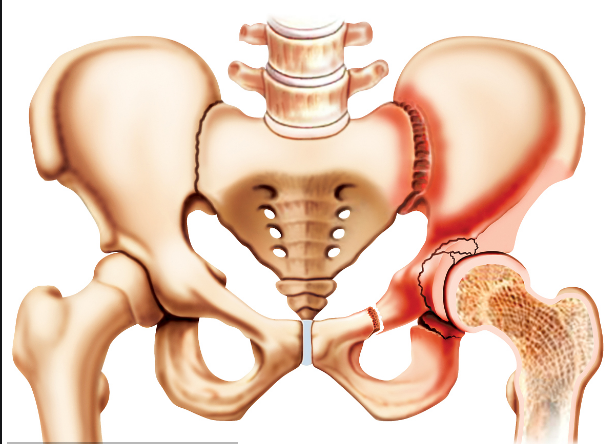

人體的髖關(guān)節(jié)是一個杵臼關(guān)節(jié),就像我們生活中常見的器物杵臼。“杵”就是我們的股骨頭,而“臼”就是指我們的“髖臼”。我們知道,正常情況下,“杵”是嵌在“臼”里面的,有豐富的肌肉保護著,但是,當(dāng)“臼”的結(jié)構(gòu)不正常時,“杵”在肌肉的作用下就會從“臼”里慢慢跑出來,導(dǎo)致無法正常發(fā)揮作用。近日,瀘州市中醫(yī)院骨三科開展的市屬醫(yī)院首例髖臼周圍截骨術(shù)PAO, 就成功為一名成年患者解決了“杵”與“臼”結(jié)構(gòu)不正常的問題。

“髖臼發(fā)育不良其根源在嬰幼兒時期已經(jīng)存在,由于未及時發(fā)現(xiàn)或治療不徹底而殘留下來 。”瀘州市中醫(yī)院骨三科主任、主任中醫(yī)師李彬介紹,肖女士的髖臼因發(fā)育不良,淺且覆蓋少,因此,造成她的髖臼對位不好。在走路時,因為力學(xué)原因,髖關(guān)節(jié)發(fā)生摩擦因而產(chǎn)生強烈的疼痛,如果沒有得到及時的根治性治療,她的病情將慢慢發(fā)展為軟骨炎,最終發(fā)生骨性關(guān)節(jié)炎,影響關(guān)節(jié)功能活動,最后不得進行髖關(guān)節(jié)置換。